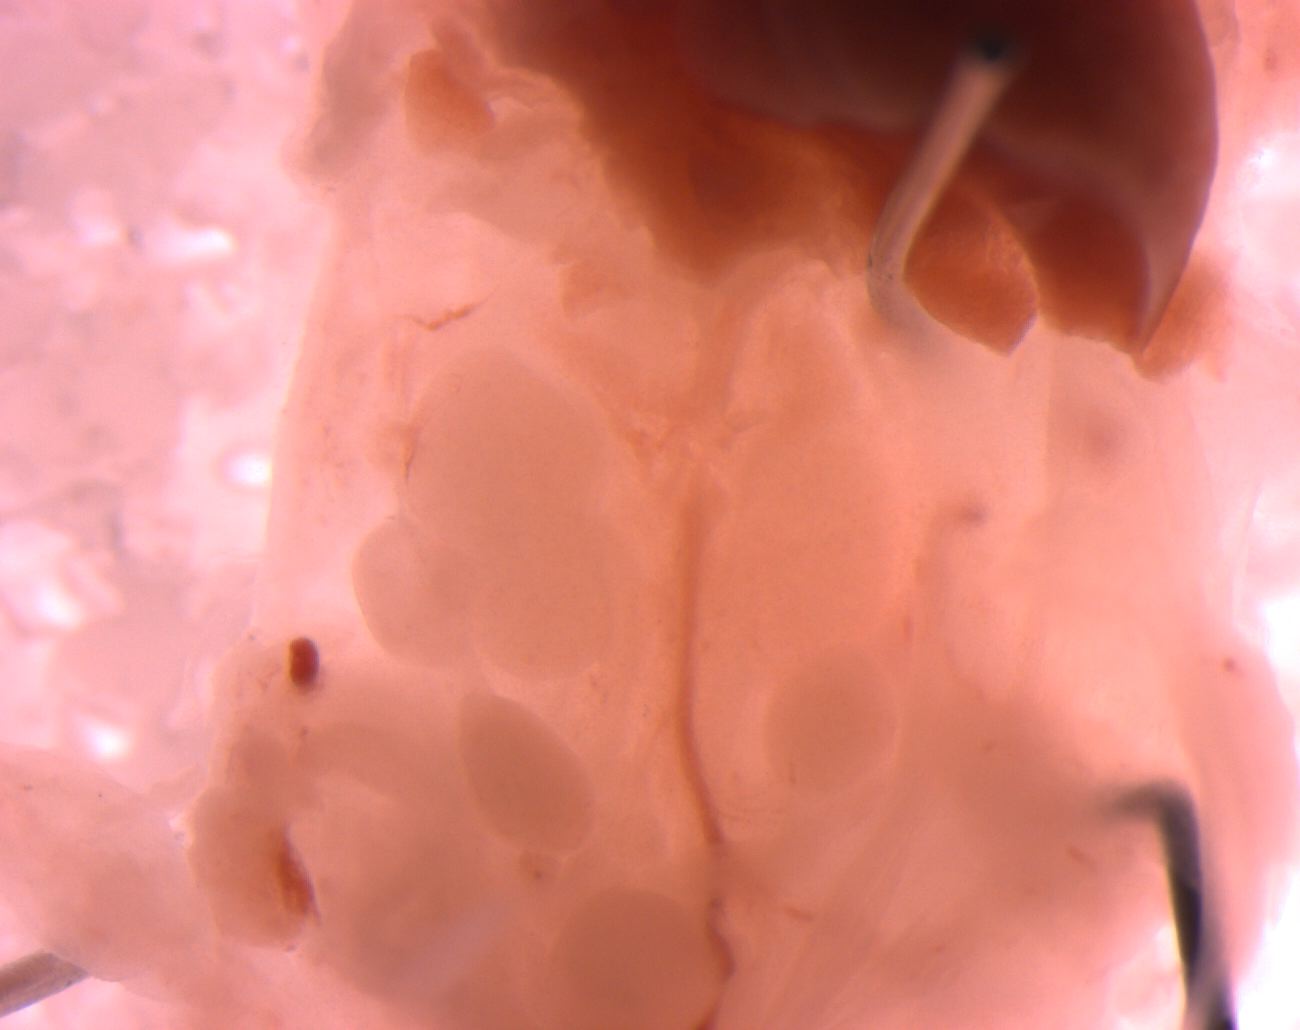

Caption Mutant 2459-003-2 (E14.5) shows cystic and dysplastic kidneys

Copyright This image is from the Laboratory of Dr. Cecilia Lo, a member of the Cardiovascular Development Consortium (CvDC), Bench to Bassinet (B2B) program of the National Heart Lung and Blood Institute (NHLBI), and is displayed with the permission of the authors. J:175213

b2b2459Clo Mutant line 2459; Bench to Bassinet Program (B2B/CVDC), mutation 2459 Cecilia Lo

b2b2459Clo/b2b2459Clo C57BL/6J-b2b2459Clo